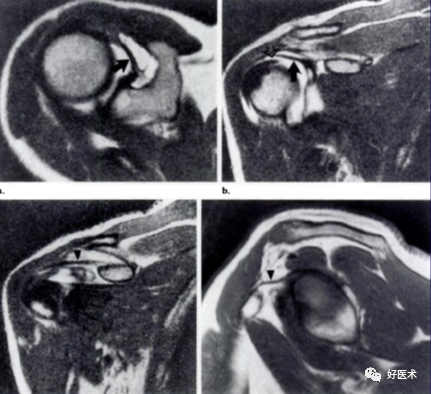

盂下隐窝:Ⅱ型或Ⅲ型BLC所致盂唇与关节盂之间的隐窝,位于12点钟方位。

盂下孔:需与盂下隐窝鉴别,位于2点钟方向

索状中盂肱韧带

Buford 复合体:索状中盂肱韧带伴前上盂唇缺如